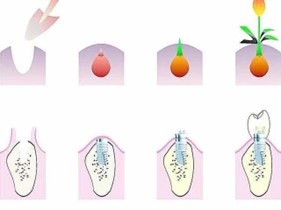

1.种植牙——“人类的第三副牙齿”

种植牙是让牙齿生根发芽吗?所谓“种植牙”,并不是一个生根发芽的过程,而是将种植体(人工牙根)通过手术植入缺牙区的牙槽骨内,一般经过3~6个月后,人工牙根与牙槽骨结合,连接基台戴上牙冠即可。而且种植牙无论从功能上,还是美观上,都非常接近人类的天然牙。

2.种植牙小演示